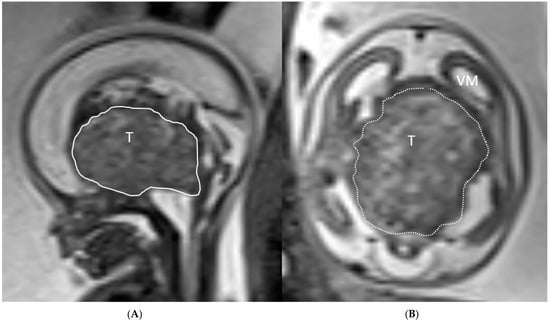

2. Case Series